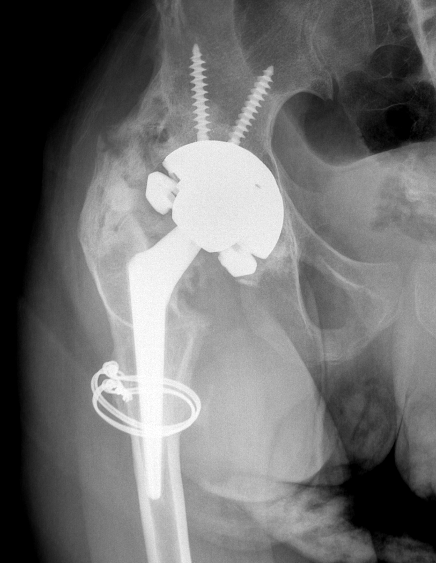

Surgical Excision

Indications

Significant symptoms / reduced ROM

Brooker III / IV

Timing

Mature HO

- cold bone scan

- serum ALP normal

Prophylaxis

Radiotherapy postoperatively as high risk

Technique

Results

Lachiewicz et al J Arthroplasty 2022

- systematic review of 7 studies and 4 patients with grade III/IV HO

- good improvement in ROM

- inconsistent improvement in pain

- irradiation prevented recurrence